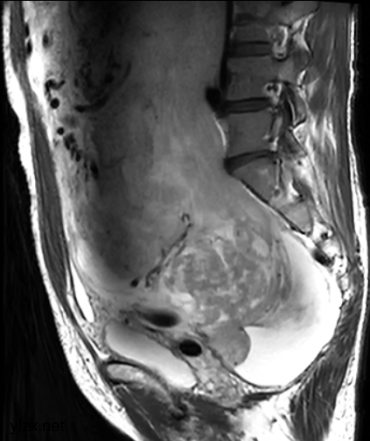

MRI检查:

子宫右侧巨大实性占位,大小约260×110×91mm,与子宫分界不清,T1WI呈稍低信号,T2WI呈不均匀稍高信号,呈束状、旋涡状改变(图1),病变内部分可见囊变,肿瘤内部及表面多发流空血管影(图2);DWI上病变呈略高信号,ADC图呈略低信号,ADC值为1.633×10-3 mm2 /s;增强扫描呈明显强化(图3),内部见条片状低信号。影像学考虑子宫右侧恶性肿瘤。

图2

子宫PEComa影像学表现各异,其MRI表现具有一定的特征,肿瘤T2WI信号稍高,呈束状排列,富血供,可伴有变性、坏死,肿瘤内部及表面可见多发流空血管影。